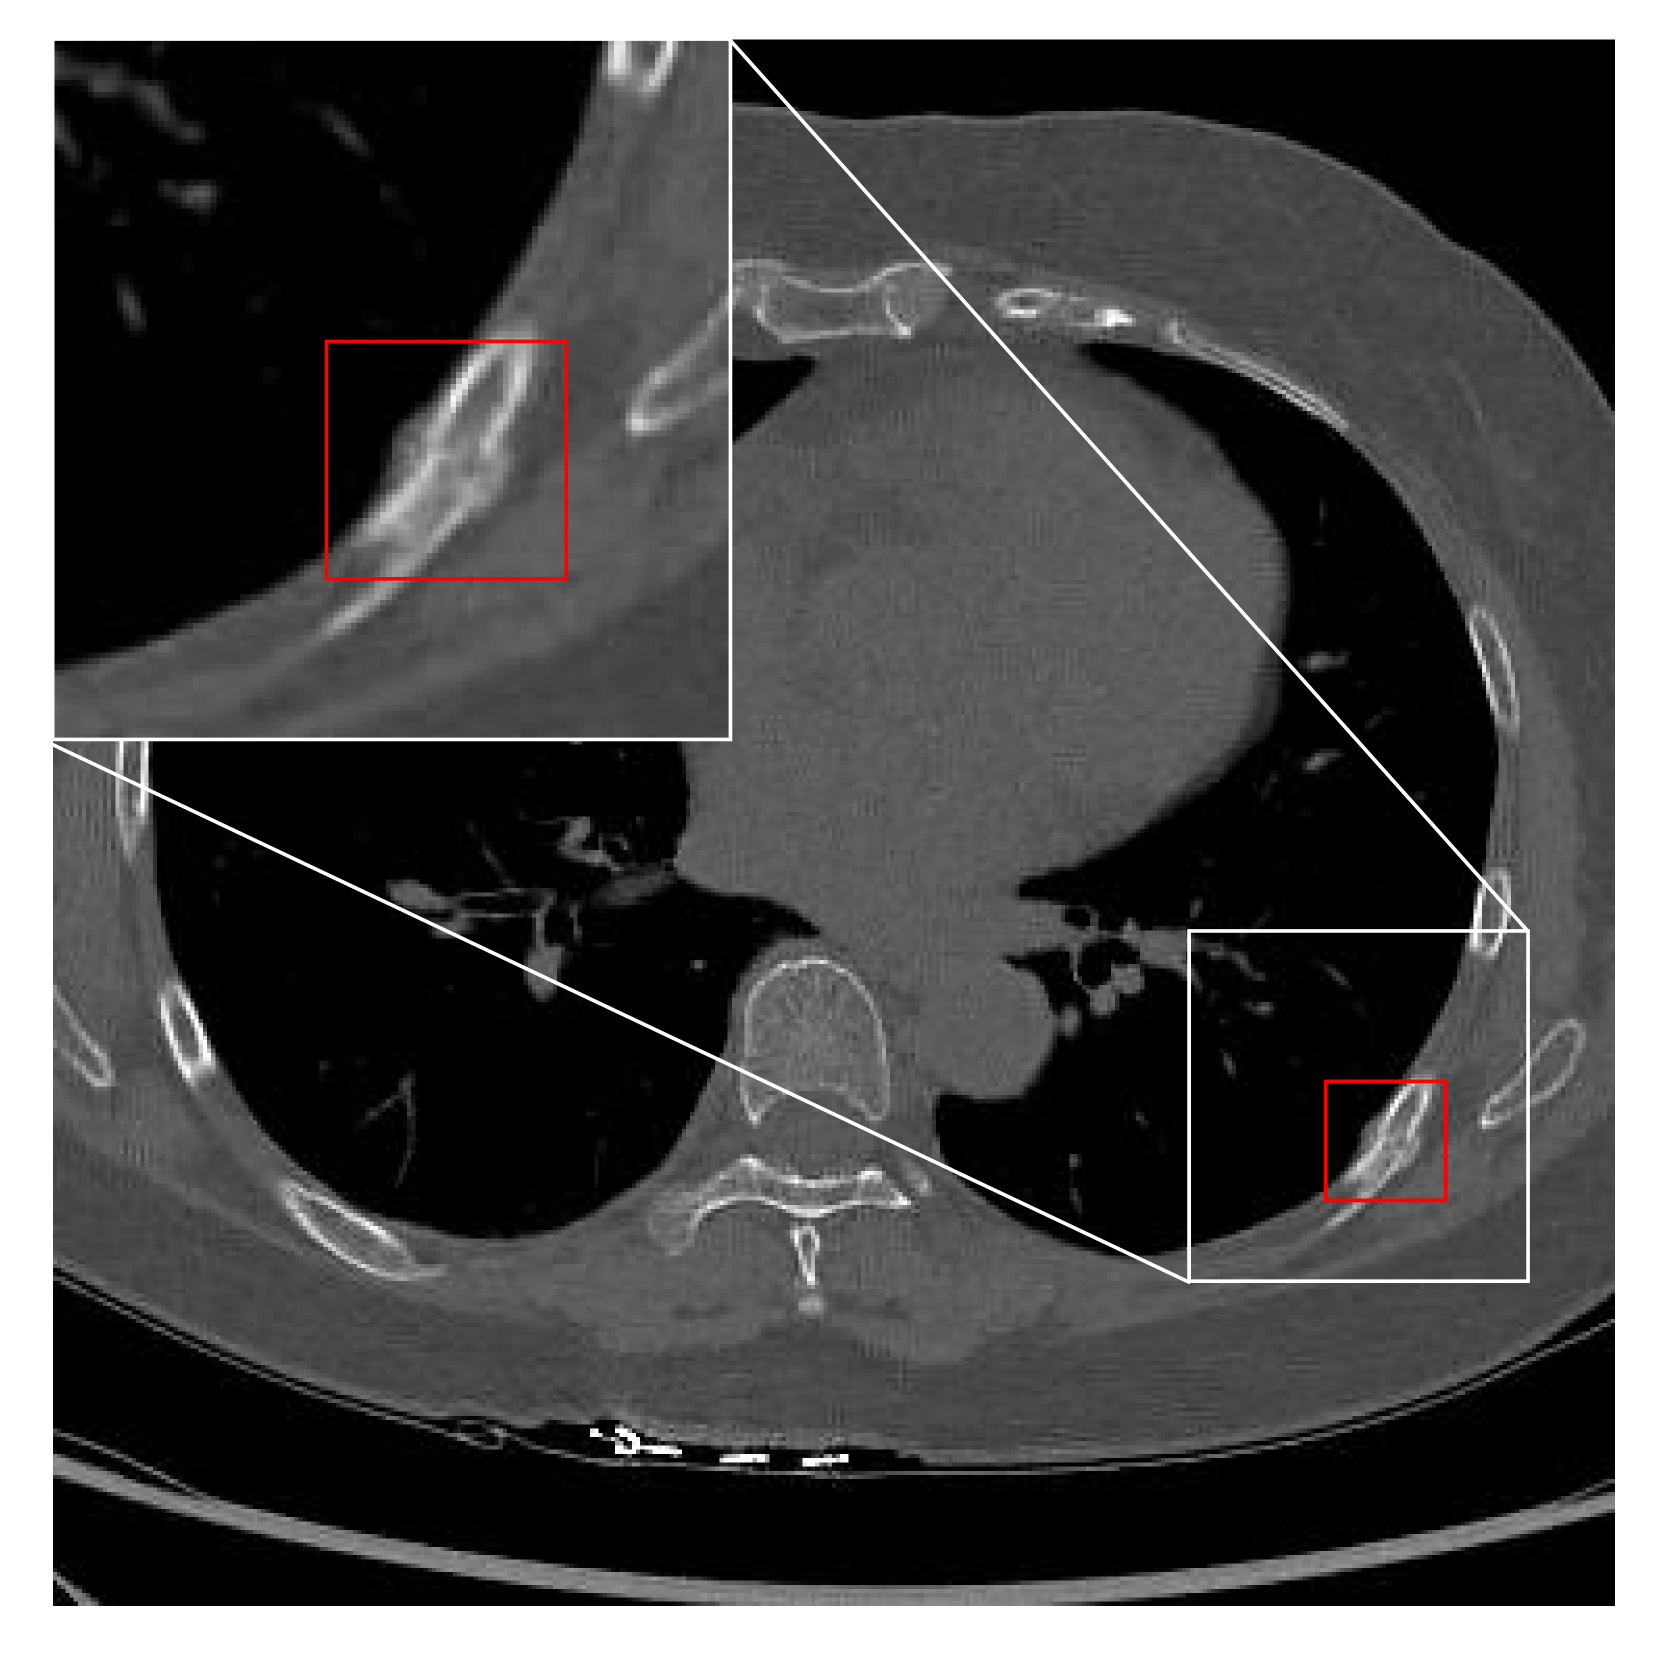

Figure 1: Medical data can have fine-grained annotations, such as (a) boxes and (b) masks, coarse-grained annotations (or weak annotations), such as (c) dots, and the data are more often (d) unlabeled. Rib fractures are highlighted by zooming in.

Despite the previous efforts to develop algorithms with less fine-grained labels, practical applications are usually faced with various forms of annotations, especially for medical data. Taking rib fractures on a computed tomography (CT) scan as an example, Fig. 1 shows that the lesion can be box-labeled, mask-labeled, dot-labeled, or unlabeled, given varied labeling criteria and budgets across different clinical centers. To take advantage of as much available supervision as possible, omni-supervised learning was proposed to develop unified frameworks that can be learned from data with annotations of various granularities. In general, existing omni-supervised object detection methods [11, 12, 13] were built on generating pseudo labels. For instance, Luo et al. [12] proposed a student-teacher framework that utilized a well-initialized teacher model to generate pseudo bounding boxes from weakly-labeled or unlabeled data to guide the learning of a student model.